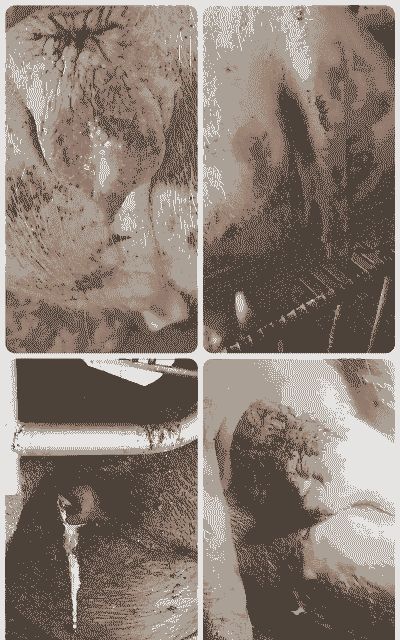

母猪产后寒是指母猪在产后出现体温降低为特征的病症,是哺乳母猪的一种常见病,尤其在严冬和春初季节多发。该病症的主要原因是饲养管理不当、猪舍潮湿、气温突变导致寒邪入侵,以及长期饲料冰冷的水料引起阳气不足和久病脾虚等。

1. 体温降低到37℃左右,呼吸微弱,畏寒打战,皮温不均,口色发青,嗜睡,四肢末端发凉,食欲废绝或减退。

2. 粪便正常或尿量减少,母猪不愿意哺乳,病情严重的还会出现呻吟,最后衰竭而死。